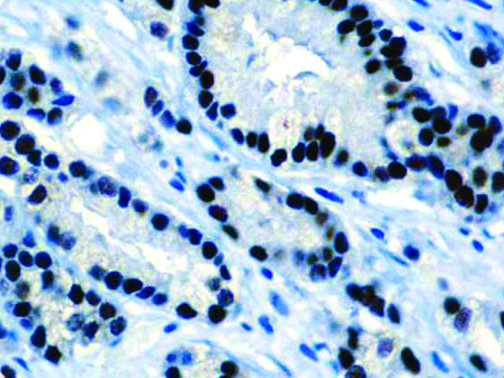

It is the ICU physician who is most likely to witness one of the deadliest manifestations of the abnormal immunological response, the cytokine storm syndrome (CSS). This response is also referred to by some as the cytokine release syndrome (CRS). CSS is characterized by continuous activation and expansion of macrophage and lymphocyte populations, which secrete large amounts of cytokines, causing the cytokine storm. This massive cytokine release is akin to hemophagocytic lymphohistiocytosis (HLH) disease, a syndrome characterized by initial unchecked and persistent activation of cytotoxic T lymphocytes and NK cells.

Clinical and laboratory manifestations of HLH include fever, enlarged liver and/or spleen, neurologic dysfunction, coagulopathy, liver dysfunction, cytopenias (i.e., low levels of erythrocytes, leukocytes, and/or platelets), hypertriglyceridemia, hyperferritinemia, hemophagocytosis, and eventually diminished NK cell activity as the immune system becomes progressively paralyzed. HLH can be familial (primary HLH) or secondary to another disease process (sHLH), such as rheumatic disease, in which it is referred to as macrophage activation syndrome (MAS, characterized by elevated ferritin).